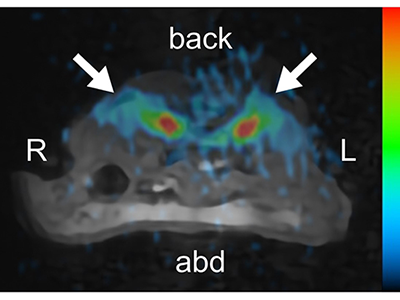

研究グループは今回、開発した23Na MRIで、実験マウスのごく小さな腎臓を撮影できるよう最適化し、より詳細かつ明瞭に撮影することを可能にした。腎臓はナトリウムの排泄や再吸収に関わっている。腎臓内には、水の効率的な再吸収が可能となる対向流増幅系といった機構が備わっており、腎臓の皮質から髄質にかけてナトリウムイオンによる浸透圧勾配が形成されている。これまで、腎臓内のナトリウムの代謝に関わるチャネルやトランスポーターについては、多くの研究が行われてきたが、腎臓内全体のナトリウム量や分布の変化については、いまだ不明な点が多く残されている。23Na MRIは、非侵襲的に腎臓全体のナトリウムの分布を評価することができ、腎臓内の、主に対向流増幅系の変化を評価することが可能だとしている。

研究では、腎臓の組織の傷害がみられない段階の早期にあたる6週齢の糖尿病モデルマウス(db/dbマウス)を用いて、同研究グループらが作成し最適化した9.4テスラの縦型磁石を用いて、MRI装置で腎臓を撮影した。

その結果、対照のマウスと比較し、腎臓内の対向流増幅系の形成が弱くなっていることが23Naを可視化した画像により明らかになった。この成果は、MRI装置を研究グループらが自作・改良し、撮像方法に独自の工夫を施したことにより得られたとしている。